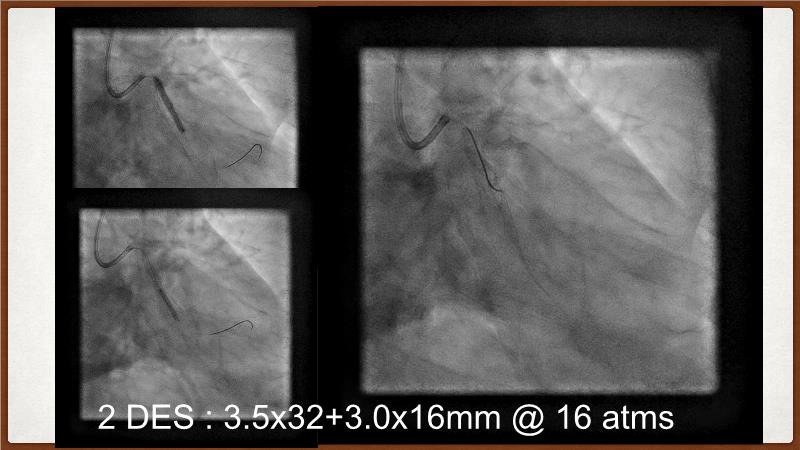

This session explores the challenges of treating calcified lesions during percutaneous coronary intervention (PCI). Learn how calcium can impede stent deliverability and expansion, potentially leading to thrombosis and restenosis. Discover the innovative Shockwave IVL technology, which uses sonic pressure waves to fracture calcium without harming surrounding tissues. The discussion also covers the ongoing challenges of calcified nodules, the importance of intracoronary imaging, and how a layered approach with multiple devices can enhance treatment outcomes. Finally, see how the IVL Shockwave C2+ device facilitates targeted energy delivery for effective PCI.

- To understand the science behind the mechanism of action of intravascular lithotripsy (IVL) for the treatment of calcified lesions

- To uncover practical tips and techniques for IVL in challenging calcified lesions: diffuse, ostial LAD bifurcations and eccentric/calcified nodules